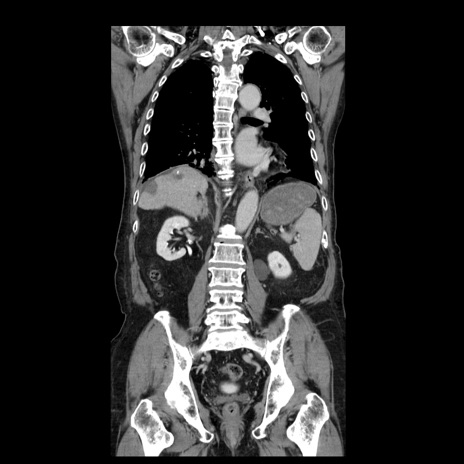

症例21(冠状断像)

【症例】70歳代男性

【主訴】腹痛

【現病歴】肝硬変・肝細胞癌にてかかりつけの方。約9時間前に食後より腹痛出現。症状が徐々に増悪し、嘔吐出現したため来院。

【既往歴】肝硬変、肝細胞癌(RFA、TACE後)

【身体所見】意識清明、表情苦悶様、BT 36℃、BP 129/78mmHg、P 88bpm、SpO2 97%(RA)、右上腹部から心窩部にかけて圧痛あり、反跳痛なし、筋性防御あり。

【データ】WBC 5800、CRP 0.16